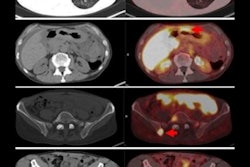

For the current study, lead author Dr. Hilde Nienhuis and colleagues used FES-PET/CT to detect a total of 1,617 metastases and normal tissue estrogen receptor expression in 91 patients with ER-positive metastatic breast cancer from November 2009 to December 2014. Each patient received an FES dose of approximately 200 MBq. Lesions with a maximum standardized uptake value (SUVmax) of 1.5 or more were considered ER-positive.

Further investigation revealed significantly higher FES uptake in bone metastases (mean SUVmax, 2.61), compared with lymph nodes (2.29, p < 0.001) and lung metastases (2.23, p = 0.021). In addition, background SUVmax varied among each organ (range: 0.7-3.3), with the greatest amount of uptake in the bones.

FES distribution and uptake in 1,617 metastases in 91 patients for bone (blue), lymph node (green), lung (red), breast (pink), brain (orange), and other (purple) lesions. Patients are categorized based on subgroups derived from the cluster analysis. Image courtesy of Dr. Hilde Nienhuis et al and JNM.Thus, the researchers detected differences between FES uptake in tumors and between patients, "underlining the heterogeneous character of breast cancer metastases in ER expression," they wrote. "Moreover, this approach better identifies F-18 FES-negative lesions."